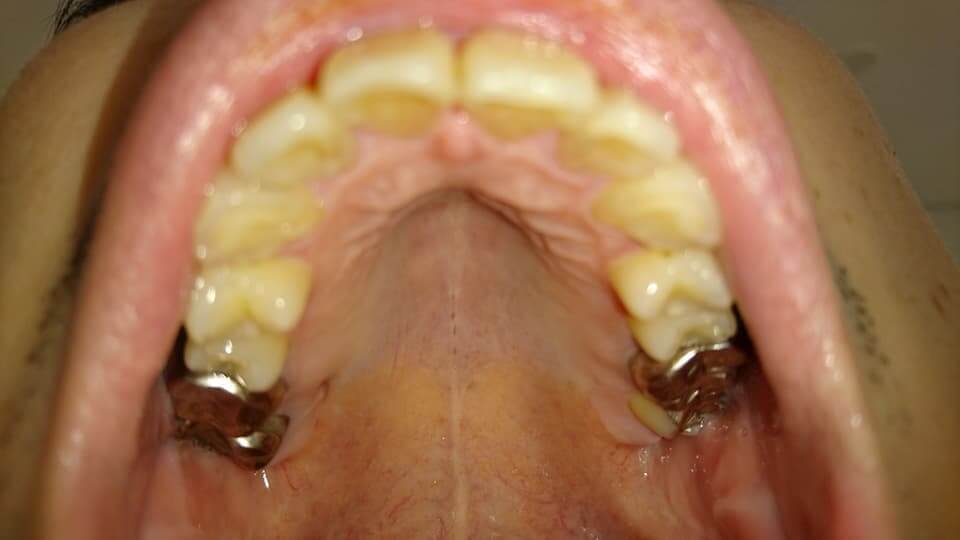

歯の写真